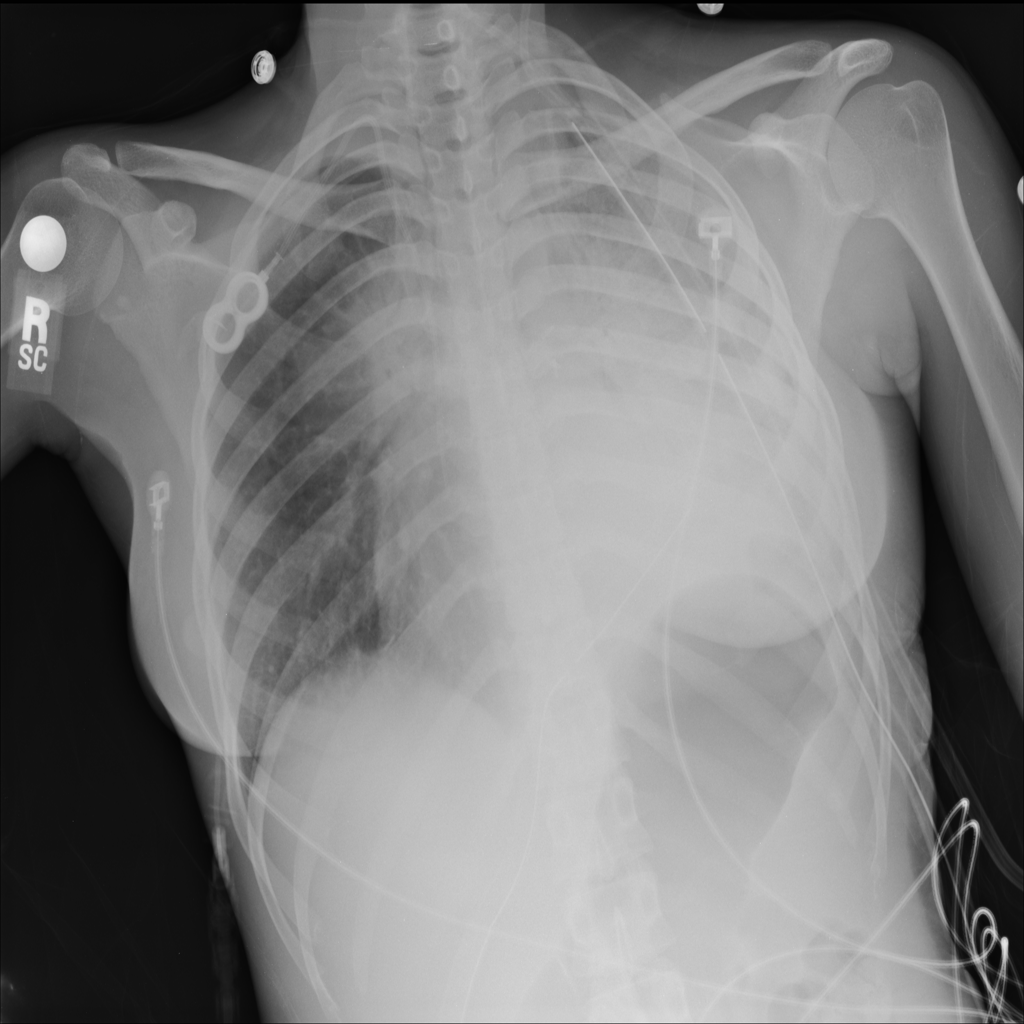

PAT-A380 · IMG-002Consolidation

PAT-A380 · IMG-002

AP